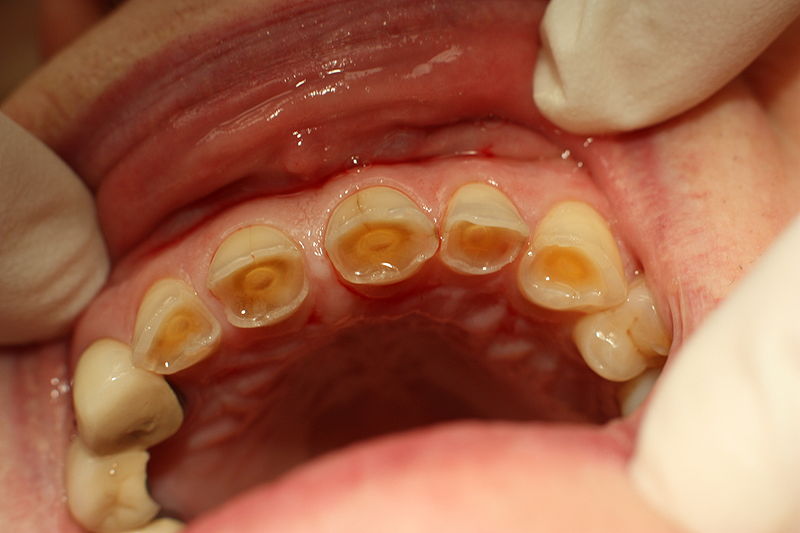

Tooth decay can appear differently depending on the stage of severity. Dentin hypersensitivity, or tooth sensitivity, can be managed effectively, and in some. You may experience more symptoms,. Dentin hypersensitivity (dh) is a condition where the dentin has become overly sensitive to thermal and chemical stimuli. These stimuli can include hot or cold It is associated with episodes of. Dentin hypersensitivity is defined as a short, sharp pain resulting from exposed dentin, in particular open dentin tubules, in response to a. Dentin hypersensitivity (dh) is a common condition that results in pain and distress. When to see a dentist. Tooth sensitivity, also known as dentin hypersensitivity, is a common dental problem characterized by sharp, temporary pain or discomfort in one or more teeth when exposed to certain stimuli.

What do dental cavities look like and when to see a dentist? Does Dentin Hurt These stimuli can include hot or cold When to see a dentist. Dentin hypersensitivity (dh) is a condition where the dentin has become overly sensitive to thermal and chemical stimuli. Tooth decay can appear differently depending on the stage of severity. Does dentin hypersensitivity go away? Dentin hypersensitivity (dh) is a common condition that results in pain and distress. Dentin. Does Dentin Hurt.